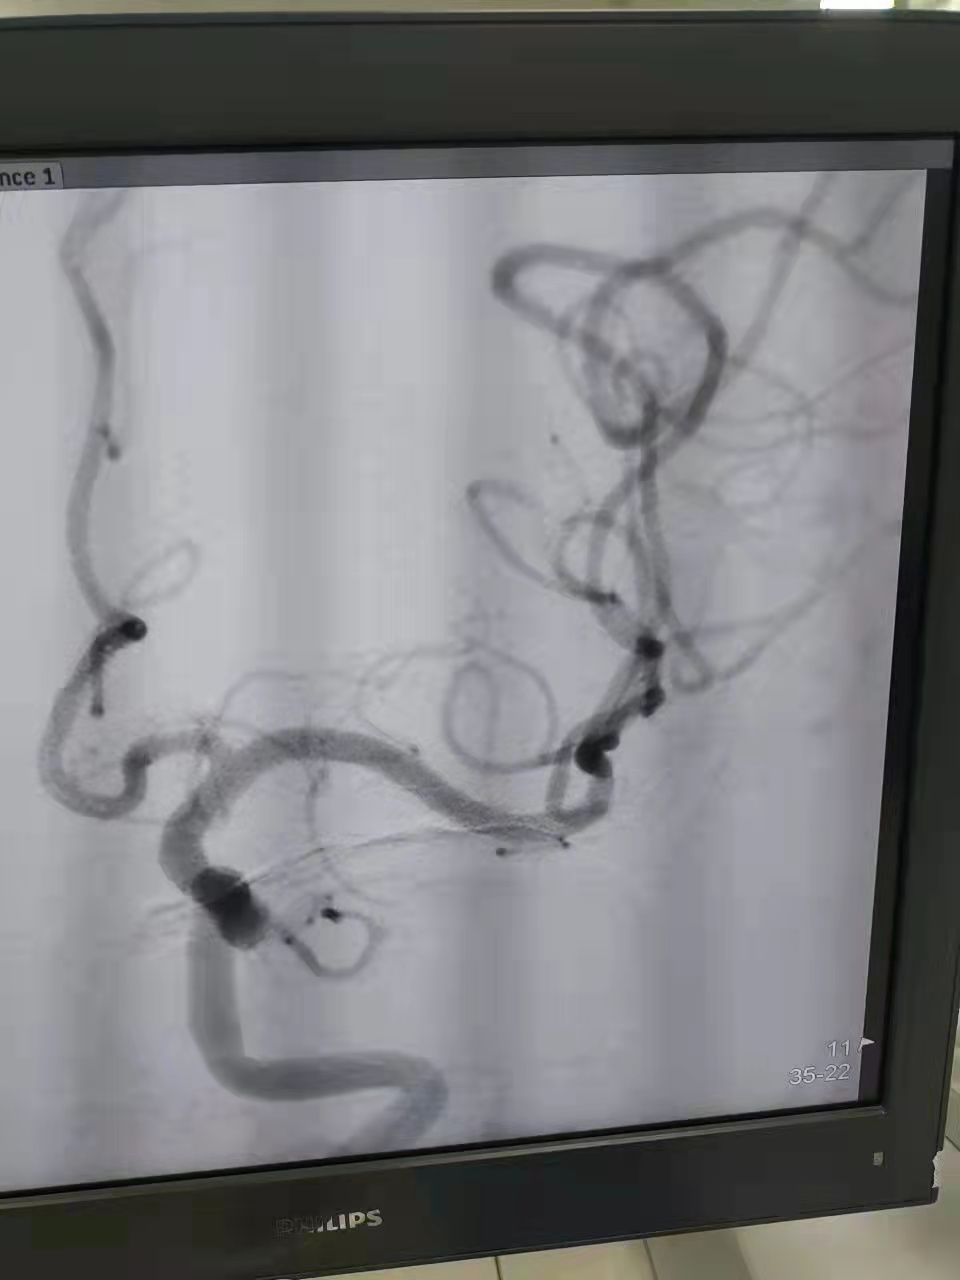

术中取出的血栓

神经内科胡华林主任及其介入团队快速制定手术方案,通过动脉抽吸血栓,再配合血管内取栓支架,1小时内快速取出了堵塞血管的血栓,陈阿姨闭塞的左侧大脑中动脉成功恢复了血流再通。手术非常顺利,陈阿姨术后言语恢复清晰,能够自由下床活动。住院3天后,省人民医院帮扶专家、心血管病专家、县人医副院长林吉进会诊,林吉进副院长针对陈阿姨心脏基础疾病及时调整用药,并叮嘱规律服药和返院复查等相关事宜,术后两周后陈阿姨顺利出院。